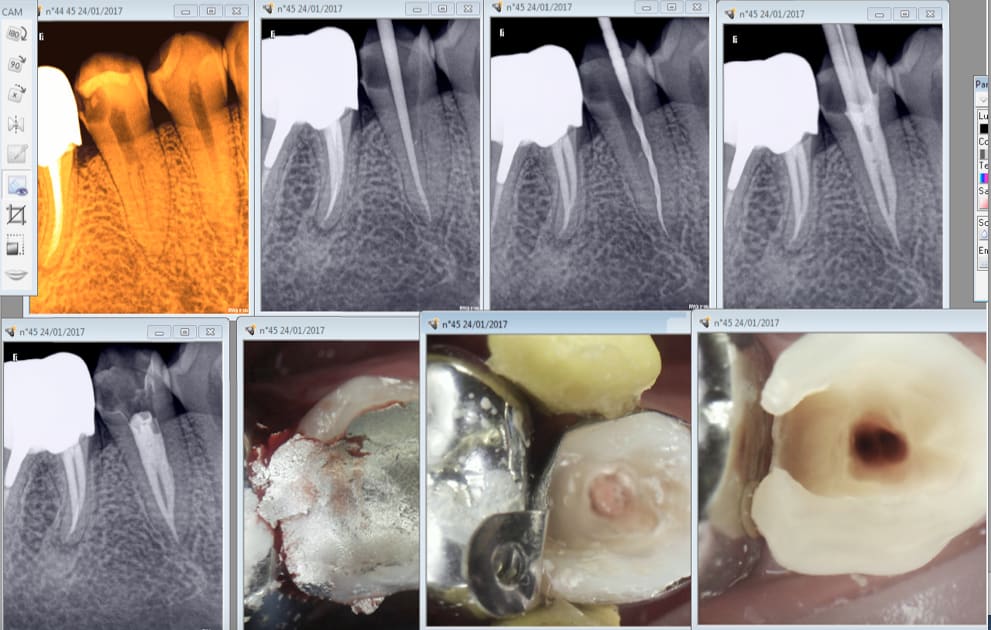

Tiens encore un exemple.

40 mn de A à Z endo taille empreinte provisoire. Et encore tu perds du temps en unitaire. Quand tu les fais en rang d'oignons tu gagnes du temps. Ca permet de réduire les couts. Ca devrait intéresser Mr Revel non ? -)